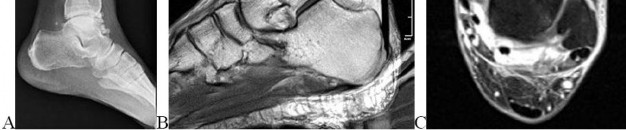

A 30-year-old male sustains an axial load to a plantarflexed foot. On physical examination, there is pronounced plantar ecchymosis and localized pain with passive pronation and abduction of the forefoot.

The primary stabilizing ligament of the disrupted joint complex connects which two osseous structures?

Explanation

Plantar ecchymosis in the midfoot is the pathognomonic sign of a Lisfranc injury. The Lisfranc ligament is an interosseous ligament that represents the strongest and most critical stabilizer of the tarsometatarsal complex. It runs obliquely from the lateral aspect of the medial cuneiform to the medial base of the second metatarsal. There is notably no direct transverse ligamentous connection between the bases of the first and second metatarsals.